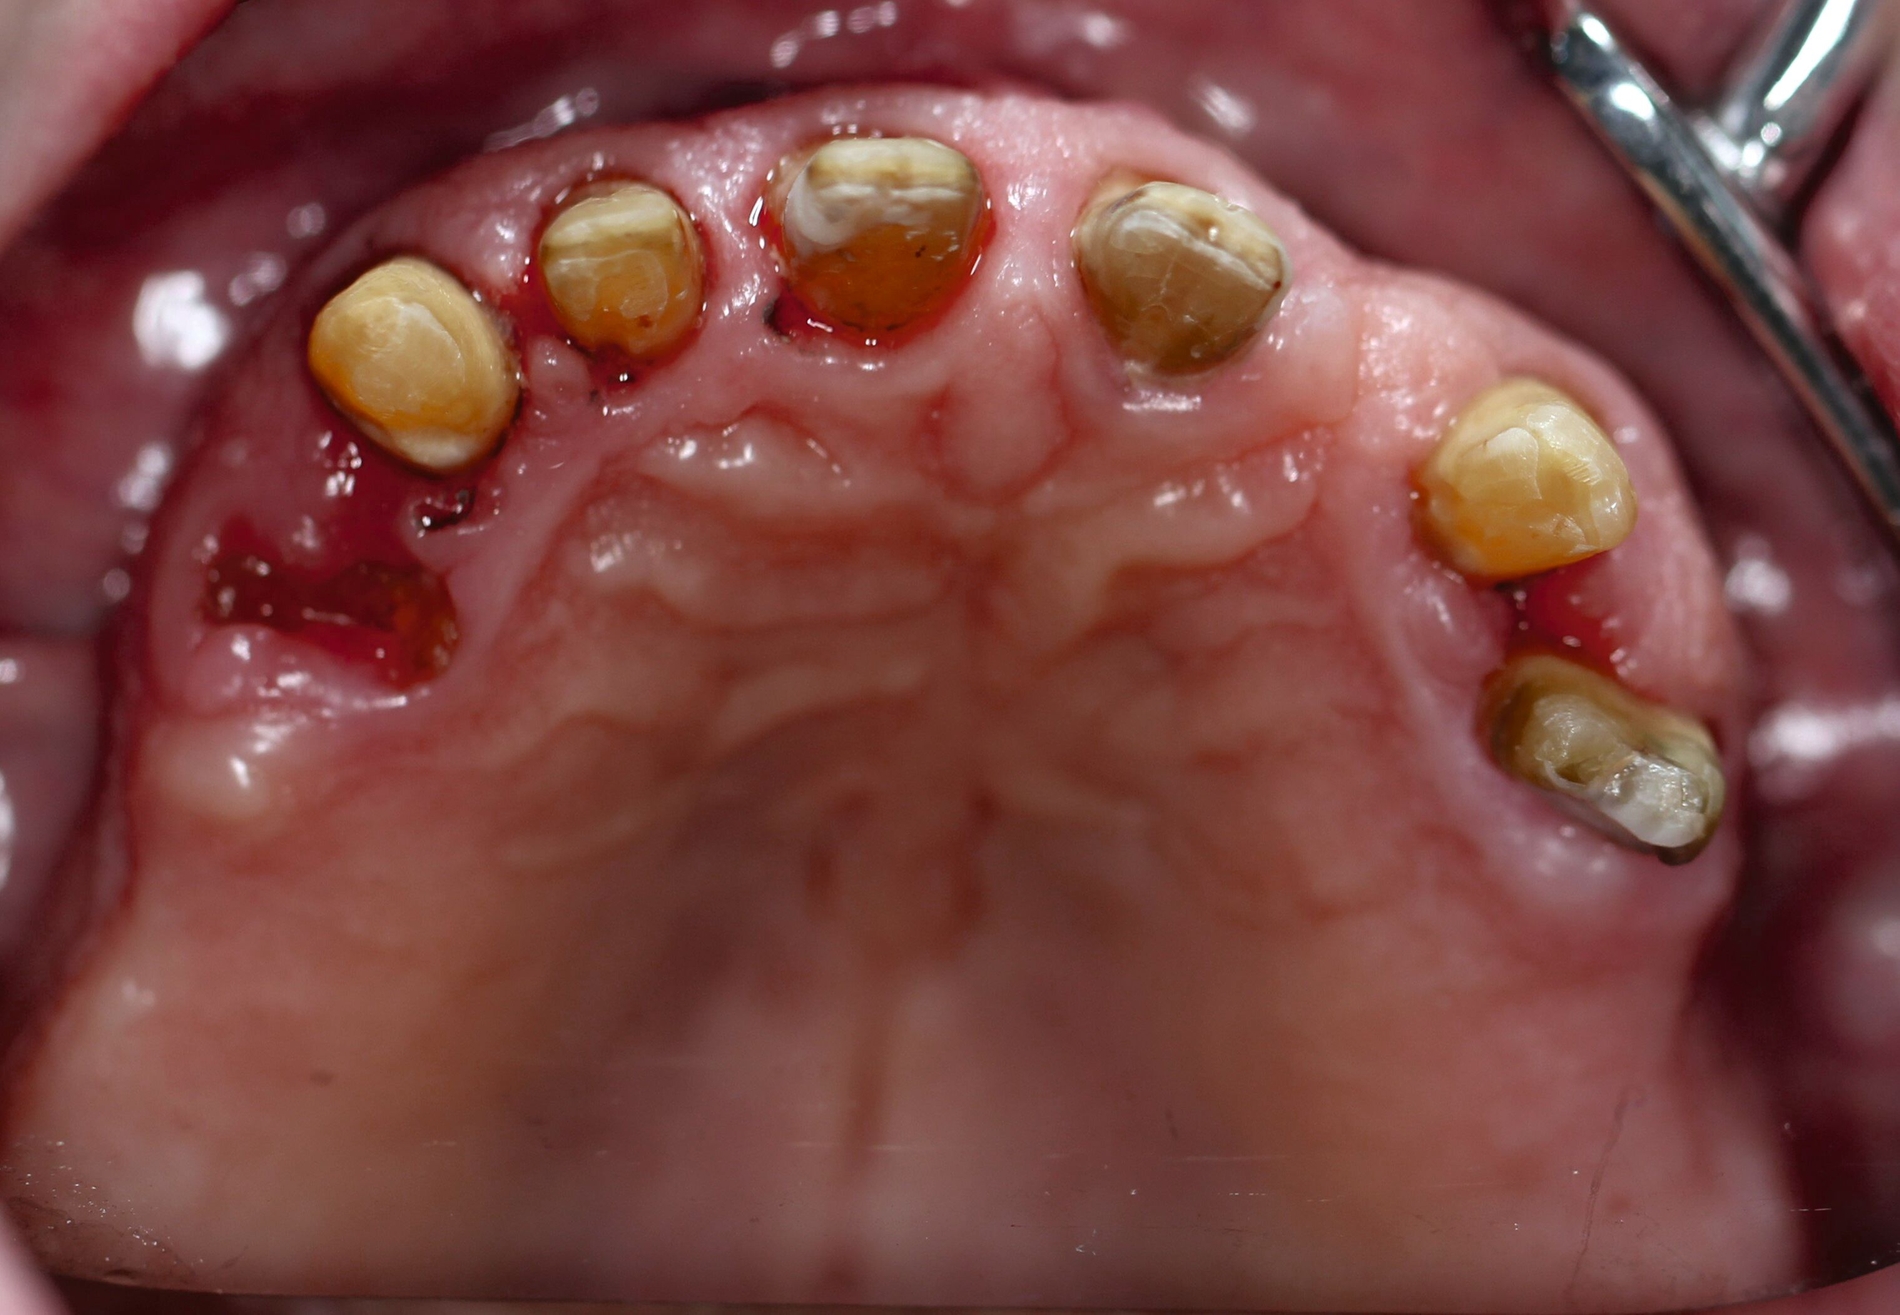

Der Patient stand unter der Dauermedikation von Metformin 500 mg, Ramipril 5 mg, Torasemid 10 mg, Metohexal 47,5 mg, Simvastatin 20 mg, Tamsulosin 0,4 mg und 3 mg Marcumar (INR 2,5–2,8) bei Zustand nach einer Bypass-Operation im Jahr 2019. Klinisch zeigten sich im Oberkiefer insuffiziente, verblockte und verblendete NEM-Kronen mit beidseitigen Gold-Extensionen distal, die über Geschiebe mit dem anterioren Anteil verschraubt waren (Abbildungen 1 und 2). Der Patient berichtete, dass die vorhandenen Kronen und Brücken 1984 eingesetzt worden seien.

Besonders auffällig war eine Dezementierung, die klinisch durch rechtsseitigen Druck und Zug mit einer Pinzette und daraufhin austretende Sulkusflüssigkeit in Regio 14 detektiert wurde. Da entsprechend des synoptischen Behandlungskonzepts [Naumann et al., 2010] bei prothetischer Neuversorgung eine gesamte Evaluation der Restpfeiler erfolgen muss, wurden zunächst die Kronen im Oberkiefer durch Schlitzen und Aufbiegen entfernt. Erst danach ließ sich deren Erhaltungswürdigkeit abschließend beurteilen.

So war der Zahn 14 tief kariös zerstört und nicht-erhaltungswürdig, was mit dem Bild der wahrscheinlich seit Längerem bestehenden Dezementierung korrelierte (Abbildung 3). Die Brücken im Unterkiefer wurden als suffizient befundet. Die Ruheschwebelage wurde mithilfe des Zielinsky-Zirkels auf 2 mm bestimmt. Parodontologisch zeigten sich stabile Verhältnisse. Ein Parodontaler Screening-Index (PSI) wurde erhoben (3-1-1-1-2-2). Der hier auffällige Zahn 14 wurde bereits zuvor beim klinischen Befund als nicht-erhaltungswürdig eingestuft und im Verlauf extrahiert.